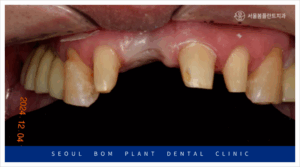

양측 위아래 어금니의

임플란트 보철물이 마무리되고 나서

앞니 심미보철치료를 진행하였는데요.

앞니는 심미성이 중요한

부위이다 보니 치아를 다듬기 전

환자분과 함께 색상과 모양을

꼼꼼하게 확인하는 작업을 거쳤으며

보철물 수복에

필요한 만큼의 양만 삭제하여

신경치료 없이 진행을 하였습니다.

앞니도 어금니와 마찬가지로

심미성이 높은 지르코니아

보철물로 수복해 드리면서

모든 치료를 마무리해 드렸는데요.